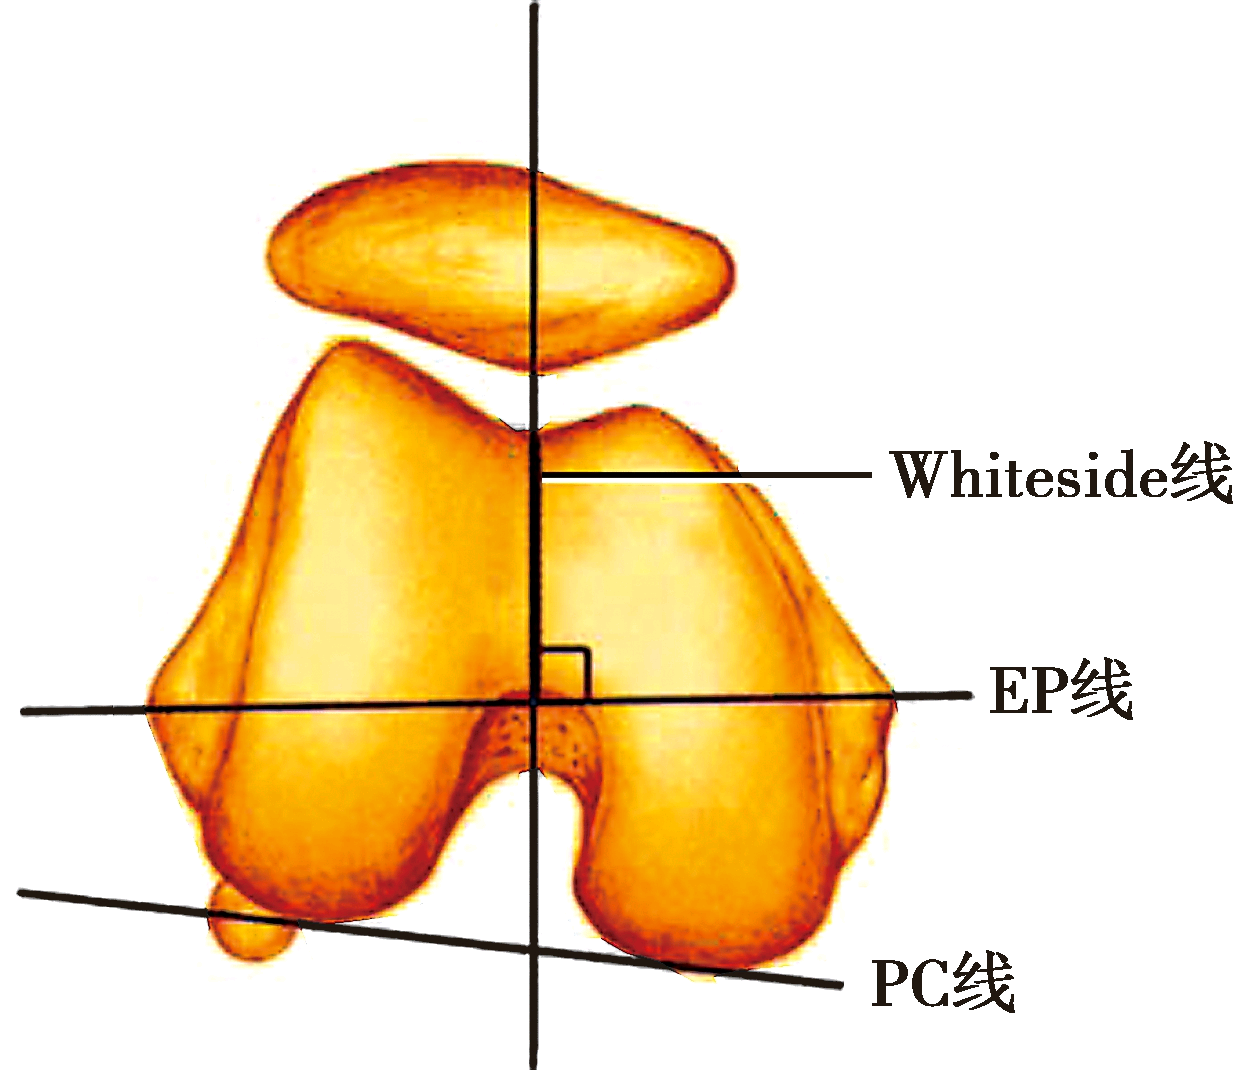

股骨旋转轴线

PC线为股骨后髁连线

EP线为股骨内外上髁连线

Whiteside线为股骨滑车切迹的最低点与股骨髁间窝中点的连线

1.骨旋转轴线

临床还可根据股骨后髁连线(posterior condylar line,PC线),股骨髁前后轴线(Whiteside线)和股骨内外上髁连线(epicondylar line,EP线)确定股骨假体安放的外旋角度。

2.PC线

最常用的参照,如果后髁的正常解剖结构遭到破坏,如膝外翻外髁磨损变小,股骨后髁连线本身也会异常内旋,如仍以此线为参照,会导致股骨假体内旋。

3.EP线

由于髌骨、韧带等软组织的阻挡,术中准确确定内外上髁最高点有一定困难,但在膝关节翻修手术中,由于股骨髁前后均有严重骨缺损,EP线可能成为唯一的参照。

4.Whiteside线

股骨髁前后轴线,即髌骨滑车最低点与股骨髁间窝中点的连线。股骨假体应与该线垂直。如果滑车发育不良或某些外翻病例,会影响股骨髁前后轴线的准确性。